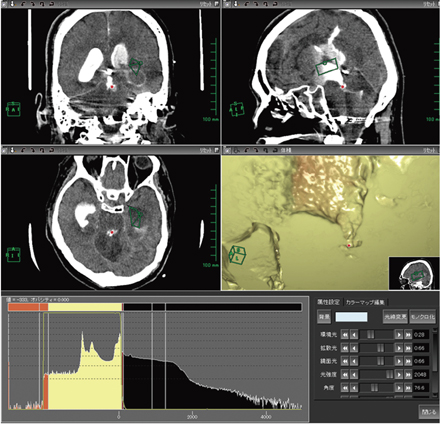

図3 AZE VirtualPlace 雷神のシミュレーション作成画面

造影剤のごく少量の通過ポイントをマーキング(●)して,AZE Virtual-Place 雷神上で仮想内視鏡画像を作成した。